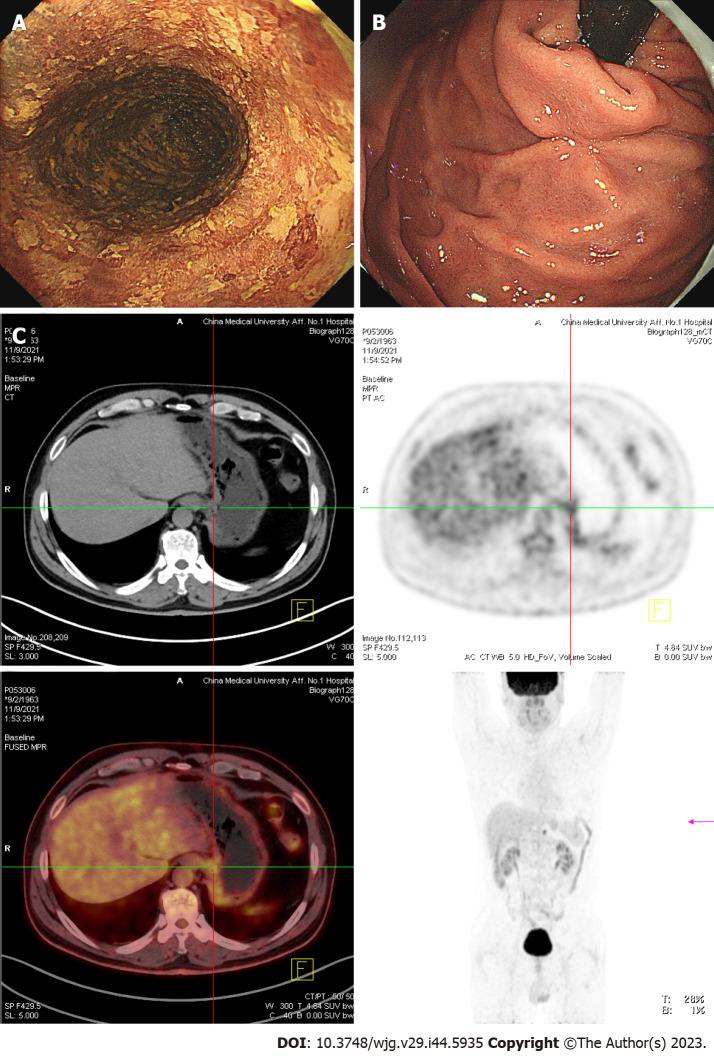

A 56-year-old man was admitted to our hospital because of a dry cough with an esophageal sensation for one year. Endoscopic examination revealed a 2.0 cm 1.0 cm, superficial esophageal squamous cell carcinoma, and the patient underwent endoscopic submucosal dissection (ESD). Fifteen months after ESD, positron emission tomography/computed tomography revealed that the metabolism of the stomach cardia wall had increased slightly. However, the mucosa of the gastric cardia was smooth under gastroendoscopy. Two years after ESD, endoscopic examination revealed a giant gastric cardia carcinoma, while the esophageal mucosa was smooth, and no advanced cancer was found. A biopsy of the gastric cardia indicated squamous-cell carcinoma. The patient received immunochemotherapy and radiotherapy for esophageal cancer for 8 mo and is currently under follow-up.

一名 56 岁男性因干咳伴食管感 1 年而入院。内镜检查显示 2.0cm×1.0cm 的表浅食管鳞癌,患者接受了内镜黏膜下剥离术(ESD)。ESD 后 15 个月,正电子发射断层扫描/计算机断层扫描显示胃贲门壁的代谢略有增加。然而,胃镜下贲门黏膜光滑。ESD 后 2 年,内镜检查显示巨大贲门癌,而食管黏膜光滑,未发现晚期癌症。贲门活检提示鳞状细胞癌。患者接受了 8 个月的食管癌免疫化疗和放疗,目前正在随访中。